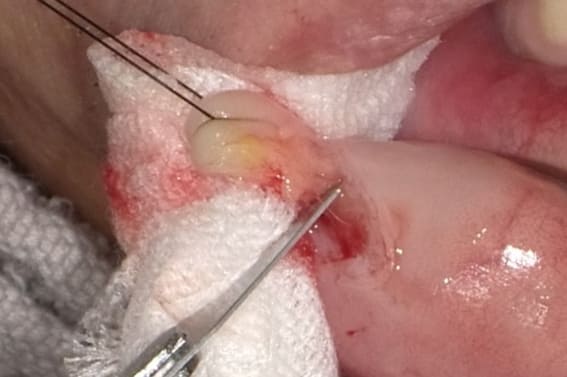

線維腫など他の良性腫瘍と同じようにカウンタートラクションを十分にかけるために腫瘍に糸をかけて十分に牽引します。ピンセットなどで把持する方法もあるが滑る可能性がありまた強く把持することで腫瘍を挫滅させる可能性もあるため糸で牽引する方がよいと考えます。いずれにしても十分なカウンタートラクションをかけながらメスを腫瘍の周りに木の葉状に切開を加えます。

腫瘍を牽引してメスを腫瘍と結合組織の間に削ぐように使い剥離することで腫瘍が周囲組織から剥離され、そのまま剥離を続けて腫瘍を摘出します。